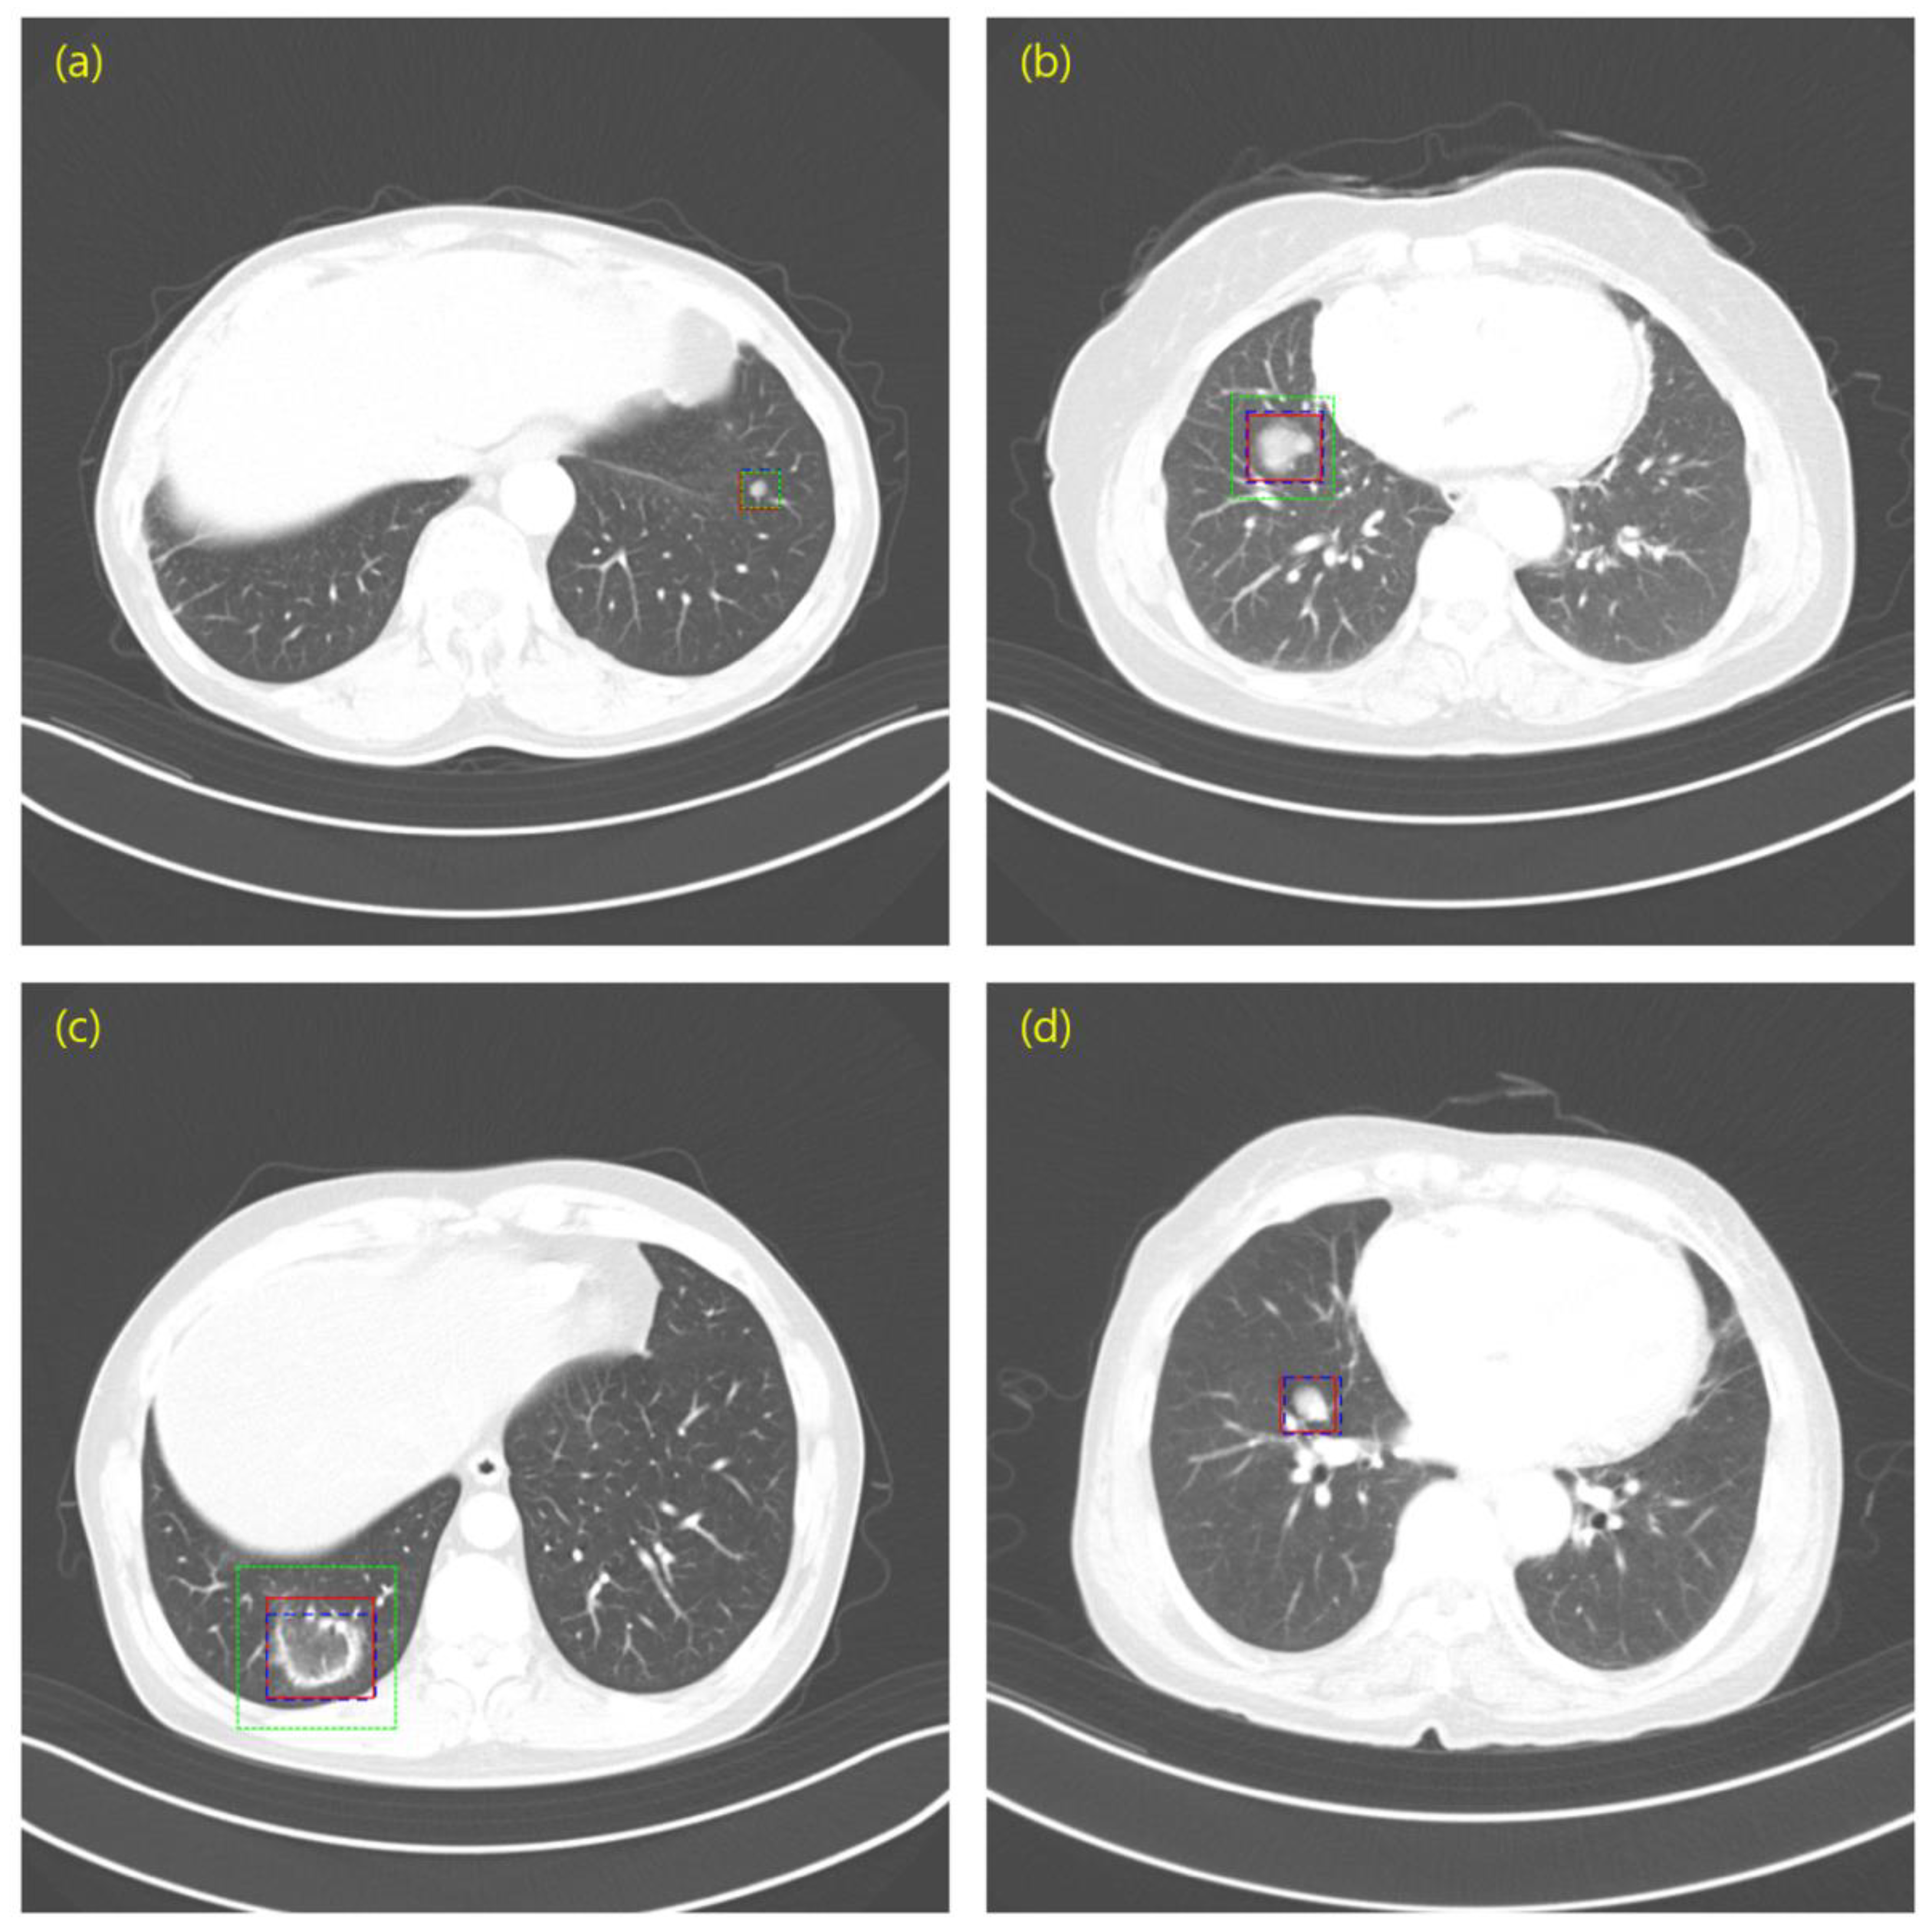

3.1. Experiment 1: Comparing the Performance of Collected Private Data and Open Data

3.2. Experiment 2: Is Pre-Training Using Open Data Effective?